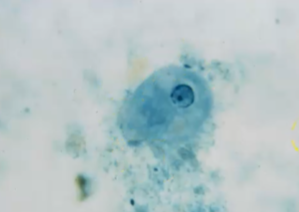

What is the species seen in this photo and WHY?

Entamoeba histolytica/Dispar CYST the dark line is a chomatoidal bar